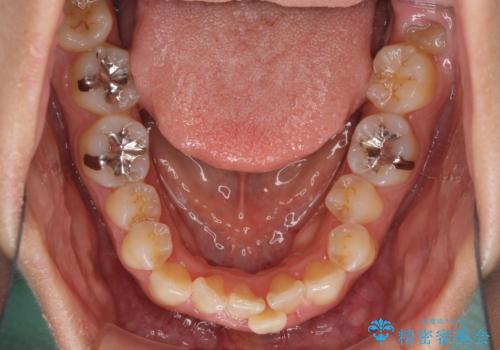

前歯のデコボコをインビザラインでスッキリと

- 上下前歯のデコボコを気にして来院された患者様です。

デコボコを解消する過程で、歯列の拡大により口元が突出する可能性があったため、4本の親知らずを抜歯しておき、歯列全体が後方に移動するように設計し、インビザラインにて矯正治療を行うこととしました。

日々の装着時間をしっかりと守って治療の臨んでくださったため、治療前のシミュレーションに近い形で矯正治療を進めて行くことができました。